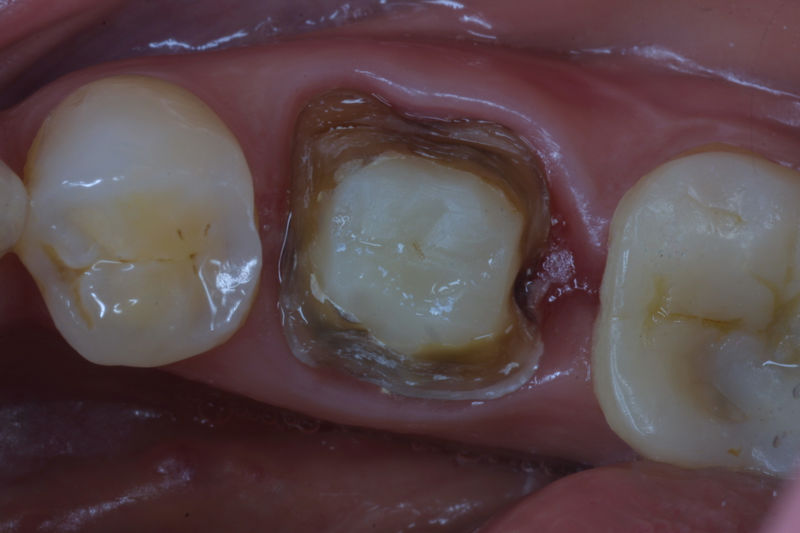

Restauraciones fabricadas en el laboratorio con materiales estéticos, los cuales cubren de manera parcial dientes posteriores. Se utilizan primariamente para restaurar dientes con caries, fracturas y/o defectos amplios. Para poder enviar el caso al laboratorio se toman impresiones utilizando materiales de impresión o técnicas modernas digitales.

Restauraciones fabricadas en el laboratorio con materiales estéticos, los cuales cubren de manera total dientes anteriores y posteriores. Se utilizan primariamente para restaurar dientes con caries, fracturas y/o defectos amplios, así como soportes de puentes. Para poder enviar el caso al laboratorio se toman impresiones utilizando materiales de impresión o técnicas modernas digitales.